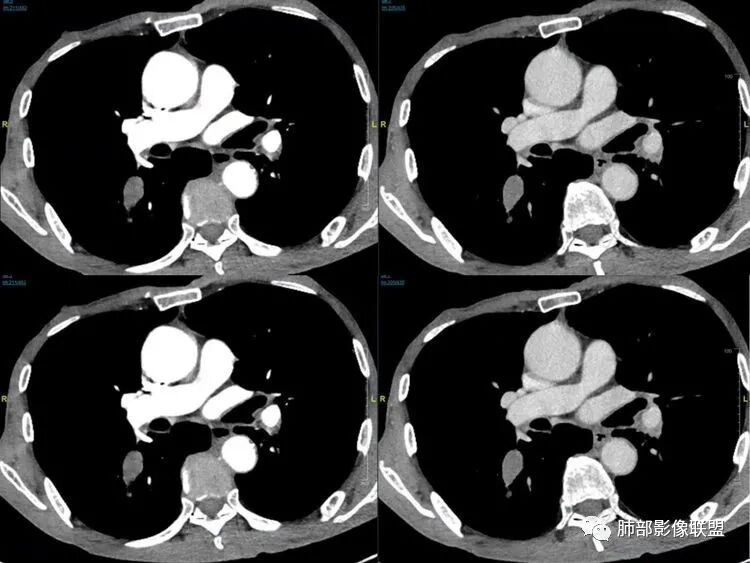

1鸭蹼状突起、腊肠样尾巴、指状突起、蠕虫、分支及条状

因为病灶沿支气管粘膜下及周围血管生长,走形方向与支气管一致,所以支气管血管周围生长也是SCLC的典型征象。当然有时会像小山丘或者灌汤包一样趴在肺边缘。

2娘小崽大、淋巴及血行转移早、冰冻纵隔及肺门、血管脂肪间隙消失

因为病灶侵袭力强,病灶易沿淋巴道、间质及心血管间隙等结构侵犯并密切挤压上述结构,常常能够观察到脂肪间隙消失。易于出现冰冻纵隔。原发灶与肺门转移灶可形成哑铃状外观,甚至转移灶体积大于周围原发灶,有人称之为“娘小崽大”。早期病灶有时很小甚或隐匿,仅能看到转移灶,或转移淋巴结与原发灶融合分界不清。病变向肺门延续的串珠样淋巴结转移也是SCLC的典型特点。

6边缘圆钝、光整,未见毛刺

神经内分泌肿瘤边缘通常圆钝,而且SCLC或周围没有任何促纤维结缔组织反应,质地软,所以边缘圆钝、没有毛刺。